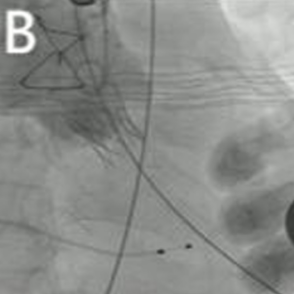

2025年6月4日,在全身麻醉下,通过TEE和荧光镜引导进行手术。通过右颈内静脉建立临时起搏。经左前外侧小切口暴露第五肋间隙,使用双重荷包缝合固定心尖;静脉注射肝素使活化凝血时间(ACT)>250秒。心尖穿刺后,先使用软导丝穿过主动脉瓣口,随后更换为Amplatz超硬导丝(波士顿科学公司)。在快速起搏(180次/分)下,使用18mm球囊对主动脉瓣生物假体进行预扩张。选择21mm ScienCrown瓣膜,旋转手柄将瓣膜从输送系统中逐步释放(视频1)。瓣膜成功植入后,无错位或瓣周漏(PVL)(图2B及视频2)。TEE显示主动脉瓣平均跨瓣压差为6mmHg,无瓣周漏(图2C及D)。随后,使用硬导丝穿过二尖瓣生物瓣进入左心房(视频3)。在快速起搏(180次/分)下于二尖瓣位置植入25mm ScienCrown瓣膜(图2E及视频4)。TEE显示二尖瓣平均跨瓣压差为5mmHg,瓣叶运动正常,无瓣周漏(图2F)。术后荧光检查显示两枚瓣膜均位置良好(图2G)。术后第一天床旁TTE显示二尖瓣压差2.52mmHg,流速0.76m/s;主动脉瓣压差13.39mmHg,流速1.7m/s,提示轻度主动脉瓣狭窄(AS)和正常二尖瓣功能(图3)。患者心功能改善至NYHA II级,并在术后第5天出院。

图2. 使用ScienCrown瓣膜进行经心尖主动脉瓣和二尖瓣ViV手术。A:18mm球囊对主动脉瓣进行预扩张。B:成功植入21mm ScienCrown瓣膜,显示无瓣周漏。C:植入后TEE确认无瓣周漏。D:术后TEE记录主动脉瓣平均跨瓣压差为6mmHg。E:二尖瓣位置25mm ScienCrown瓣膜的理想释放。F:植入后TEE评估显示二尖瓣平均跨瓣压差为5mmHg。G:术后影像学检查显示两枚植入假体瓣膜的位置及形态均正常。